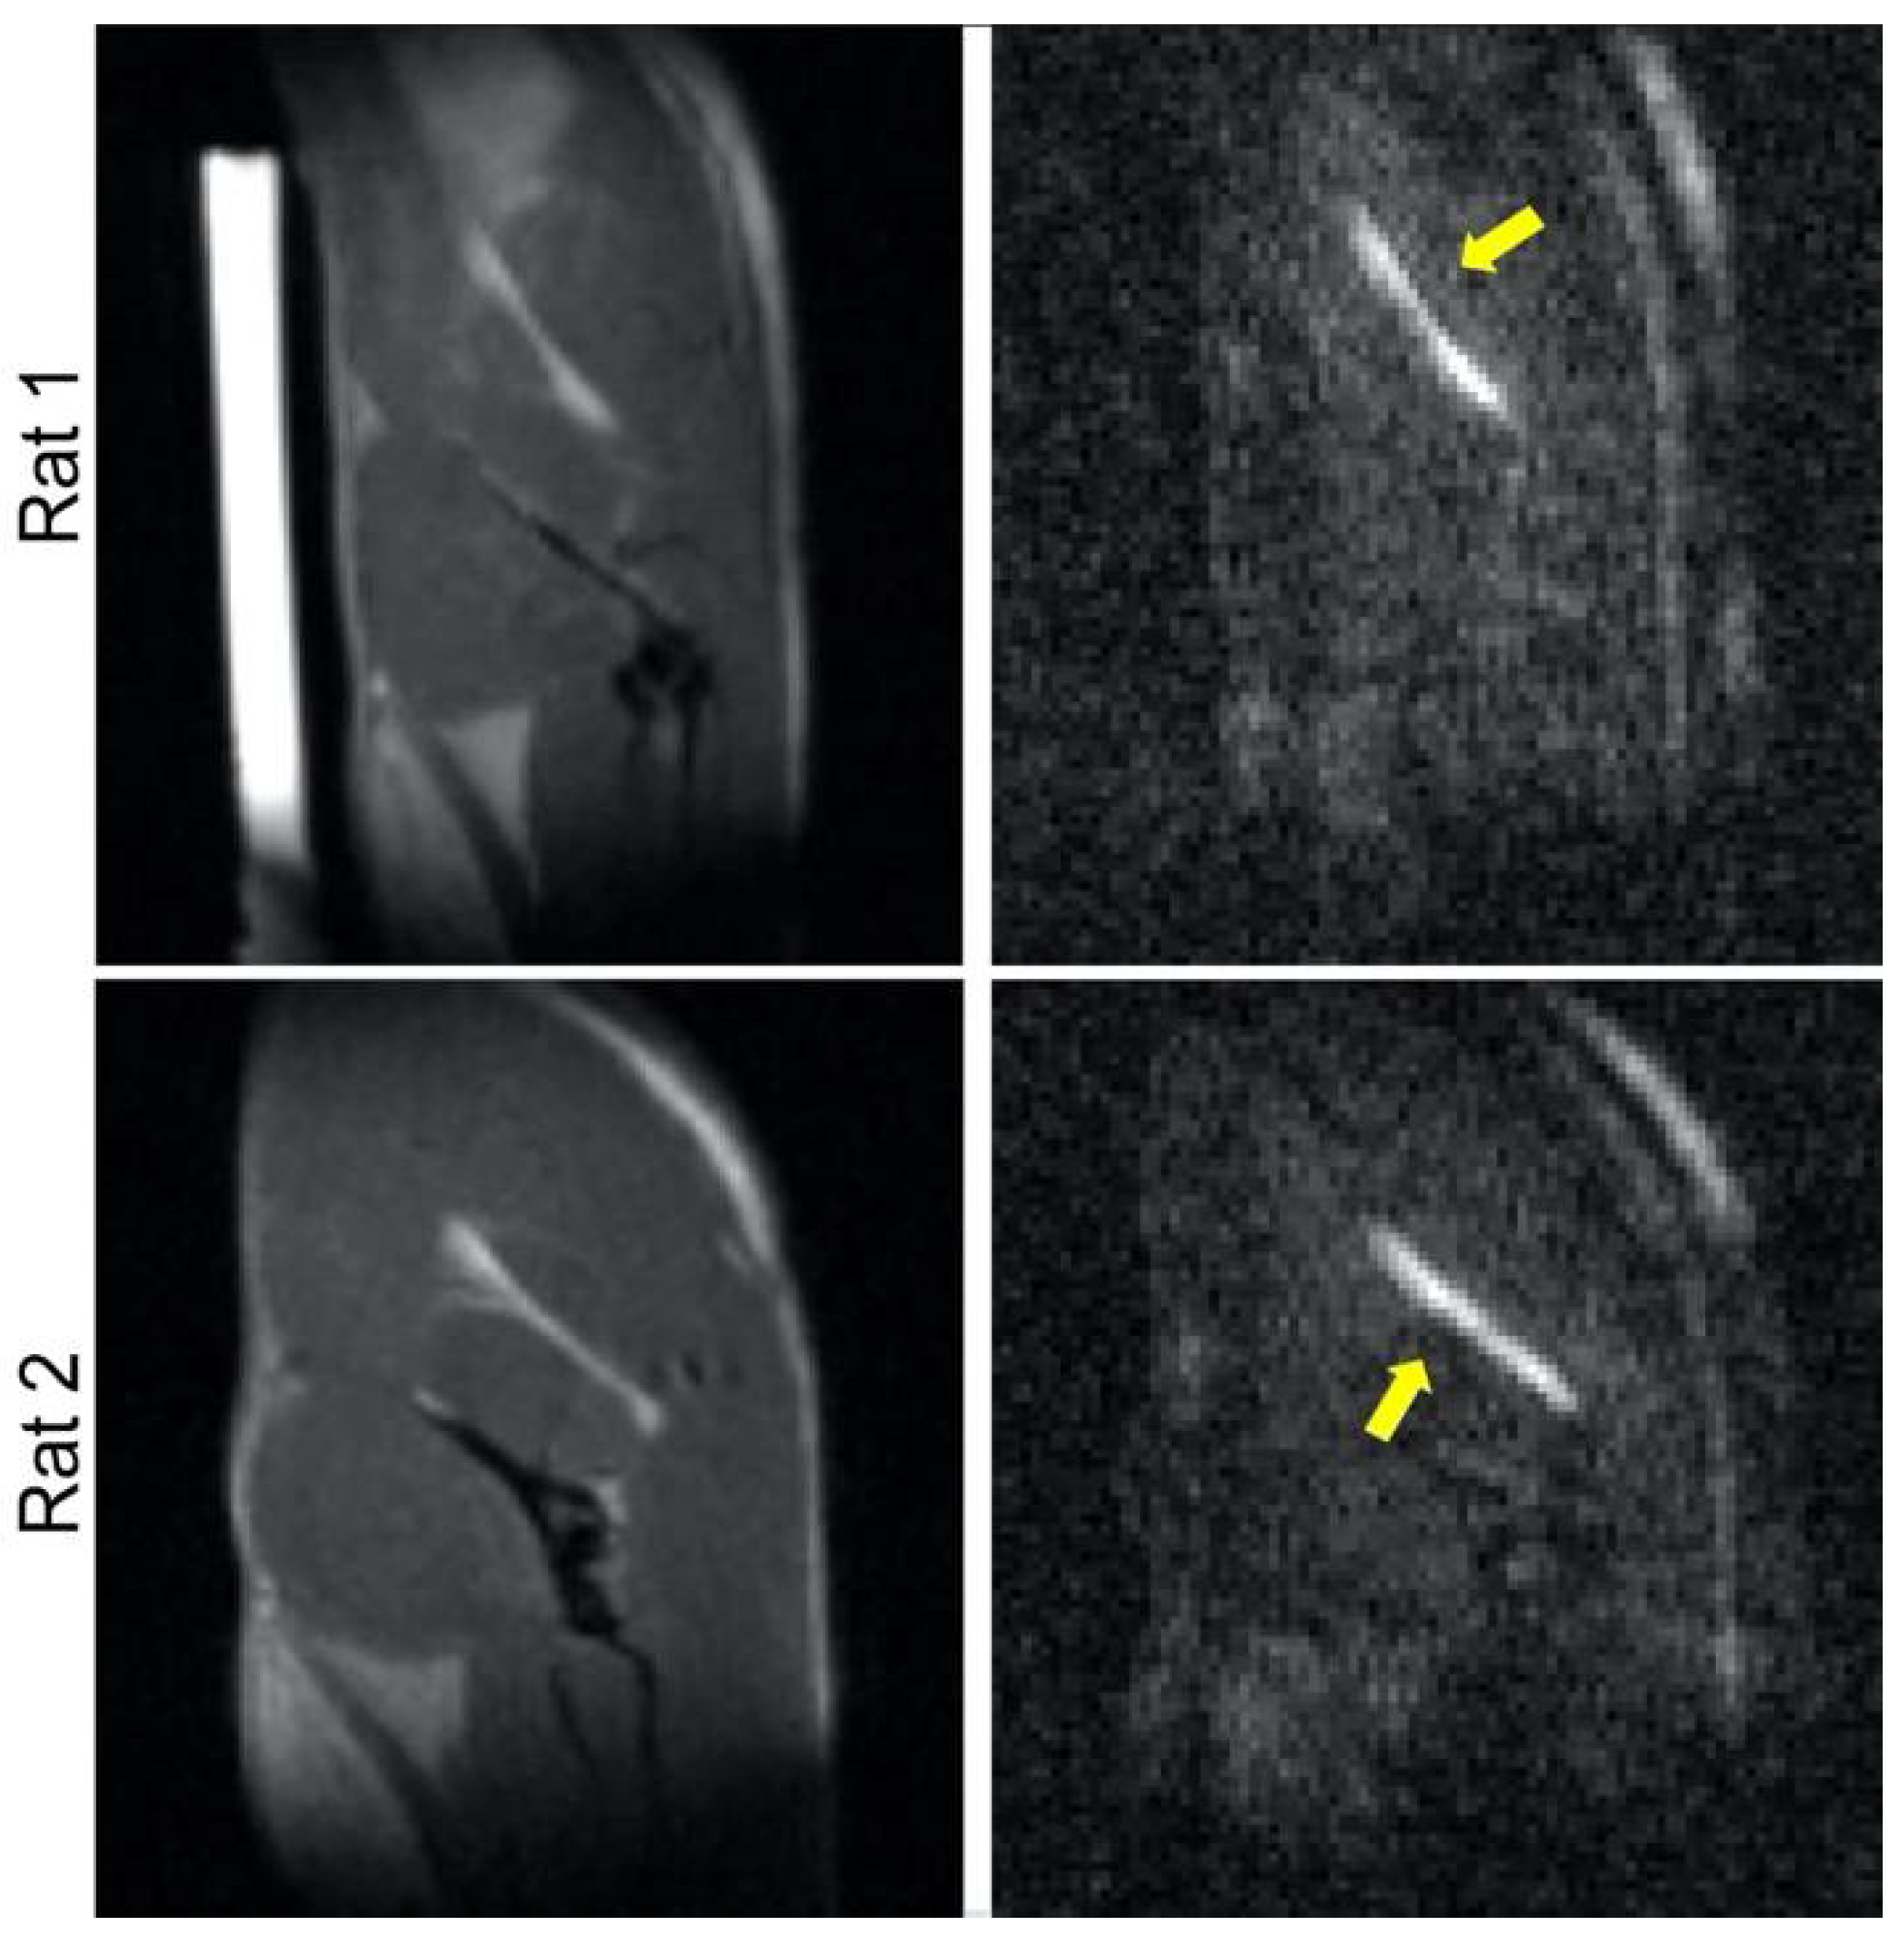

2. Materials and Methods

2.1. MRI

3. Results